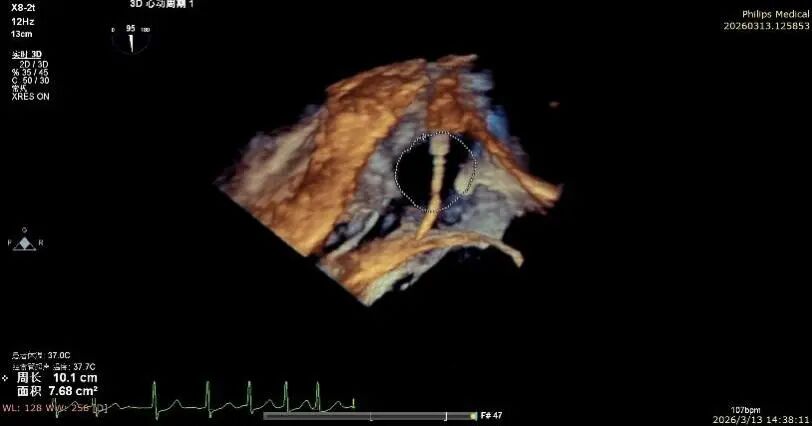

Comparison of Tricuspid Annular Area After Annuloplasty

Postoperative tricuspid annular area: 7.68 cm²

Following annuloplasty, leaflet coaptation was improved compared with the preoperative state, and regurgitation was reduced from severe to trivial.